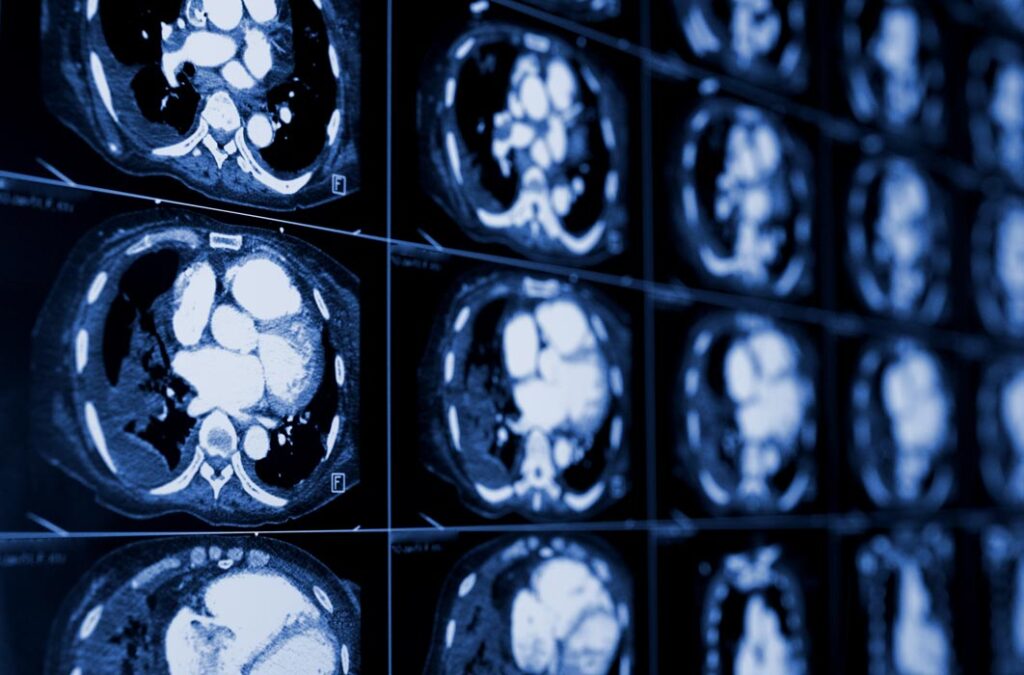

Kompjuterizovana tomografija grudnog koša, abdomena i male karlice - praktične smernice

Kurs je akreditovan kao Nacionalni kurs I kategorije od strane Zdravstvenog saveta Republike Srbije, maksimalan broj polaznika 4

termin:

20.07.2026 – 14.08.2026

Kurs je koncipiran kroz teorijsku i praktičnu edukaciju polaznika u KBC Zvezdara, Beograd.

Za lekare na specijalizaciji iz radiologije i specijaliste radiologije koji žele da obnove, nadograde i usavrše svoje znanje, steknu neophodno samopouzdanje u svakodnevnom radu i da se upoznaju sa mogućnostima savremenih dometa CT dijagnostike

Predavači su iskusni radiolozi koji godišnje u Službi za radiološku dijagnostiku obave preko 10.000 CT pregleda

Praksa se obavlja na najsavremenijem dijagnostičkim CT radnim stanicama

Rad u malim grupama (do 2 polaznika po mentoru), fleksibilno vreme održavanje praktične nastave

Cena po polazniku je 120.000 dinara (1000 €)